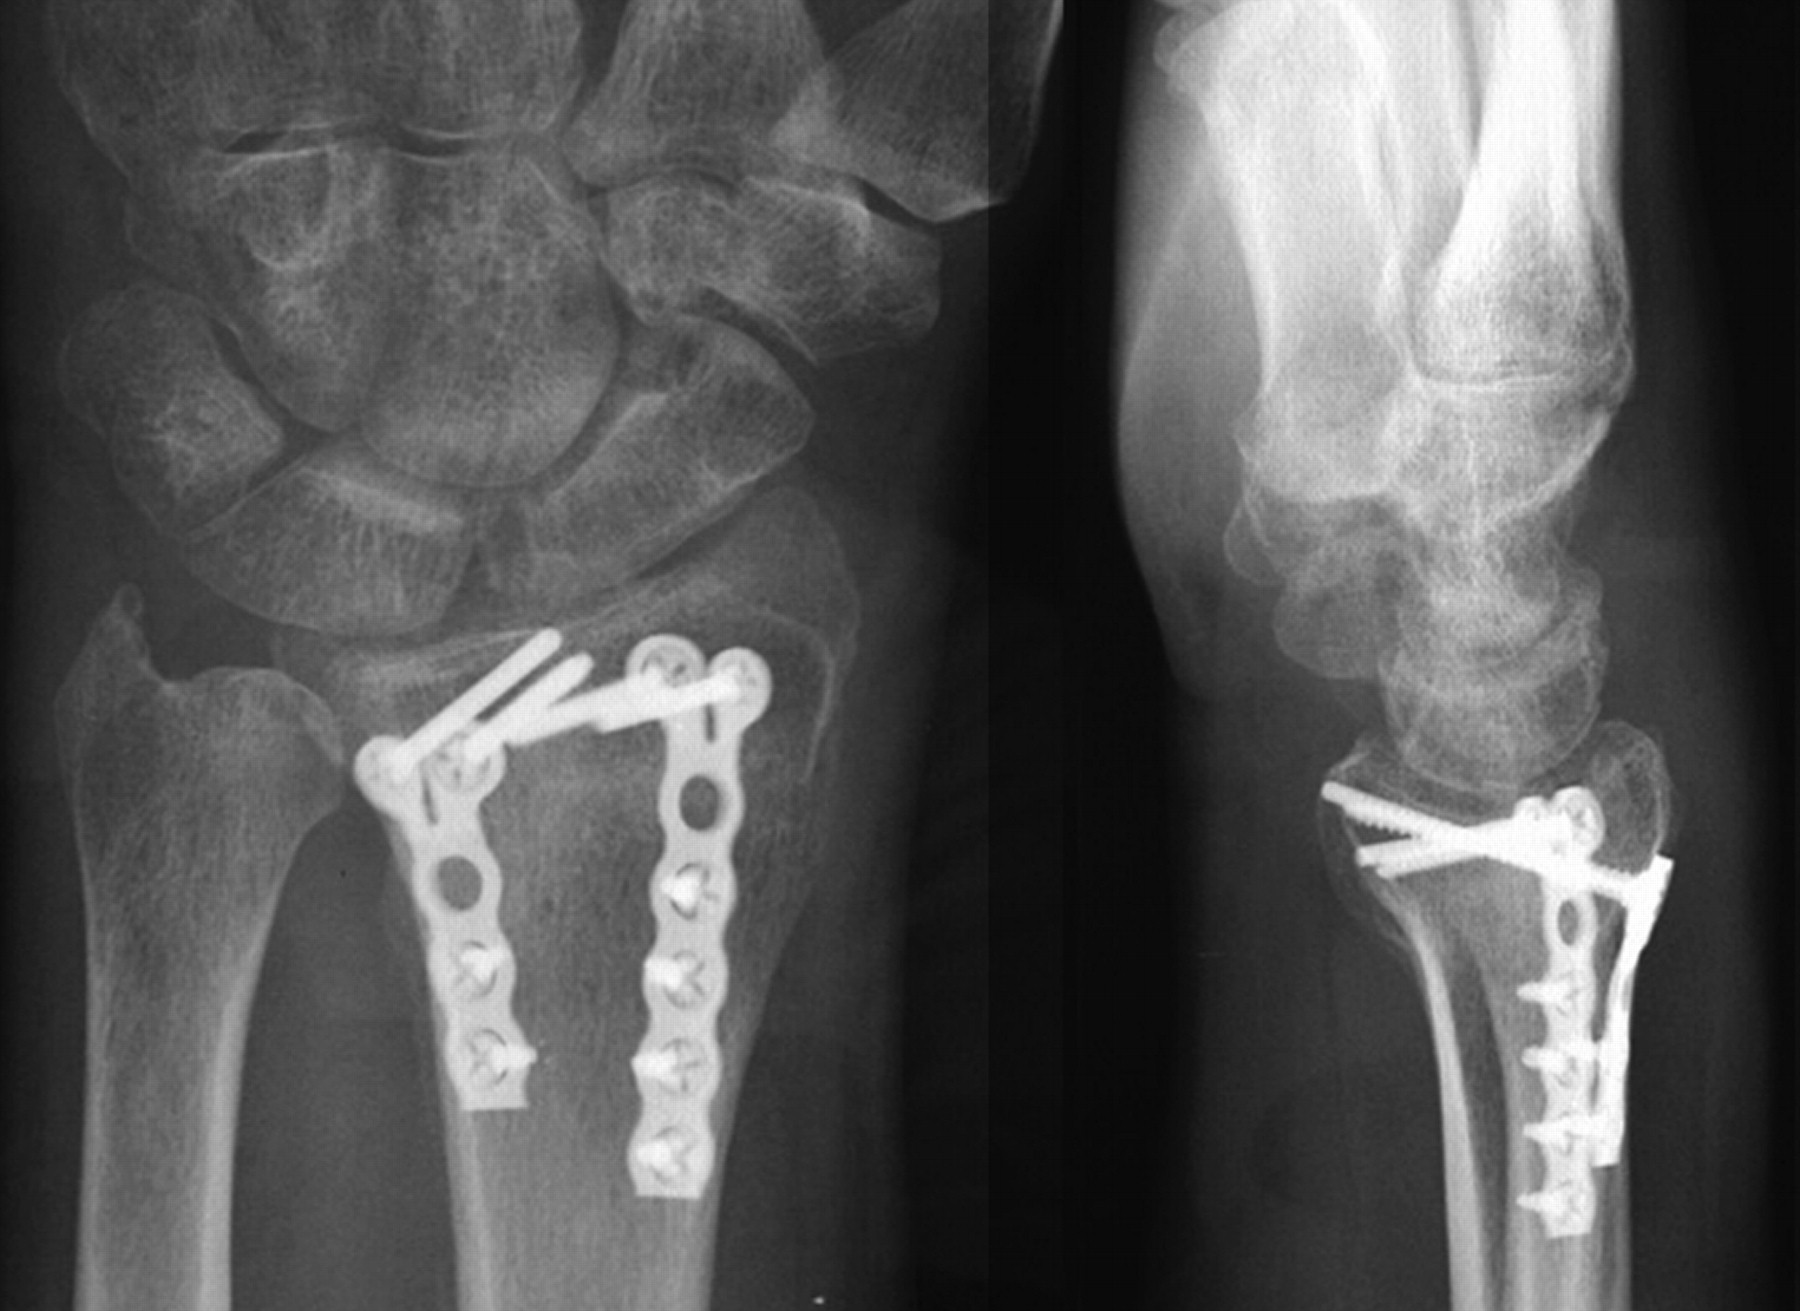

Ultimate Guide of External Fixator Orthopromed Inc. Medical

Internal Fixation for Fractures OrthoInfo AAOS Example Of Percutaneous Skeletal Fixation Percutaneous fixation offers many advantages (low risk of avascular necrosis, fibrosis and stiffness, improved cosmesis, low. Internal fixation allows shorter hospital stays, enables patients to return to function earlier, and reduces the incidence of nonunion (improper healing) and malunion (healing in improper. Fracture of the distal radius is a common clinical problem. The indications for percutaneous fixation are any unstable. Example Of Percutaneous Skeletal Fixation.